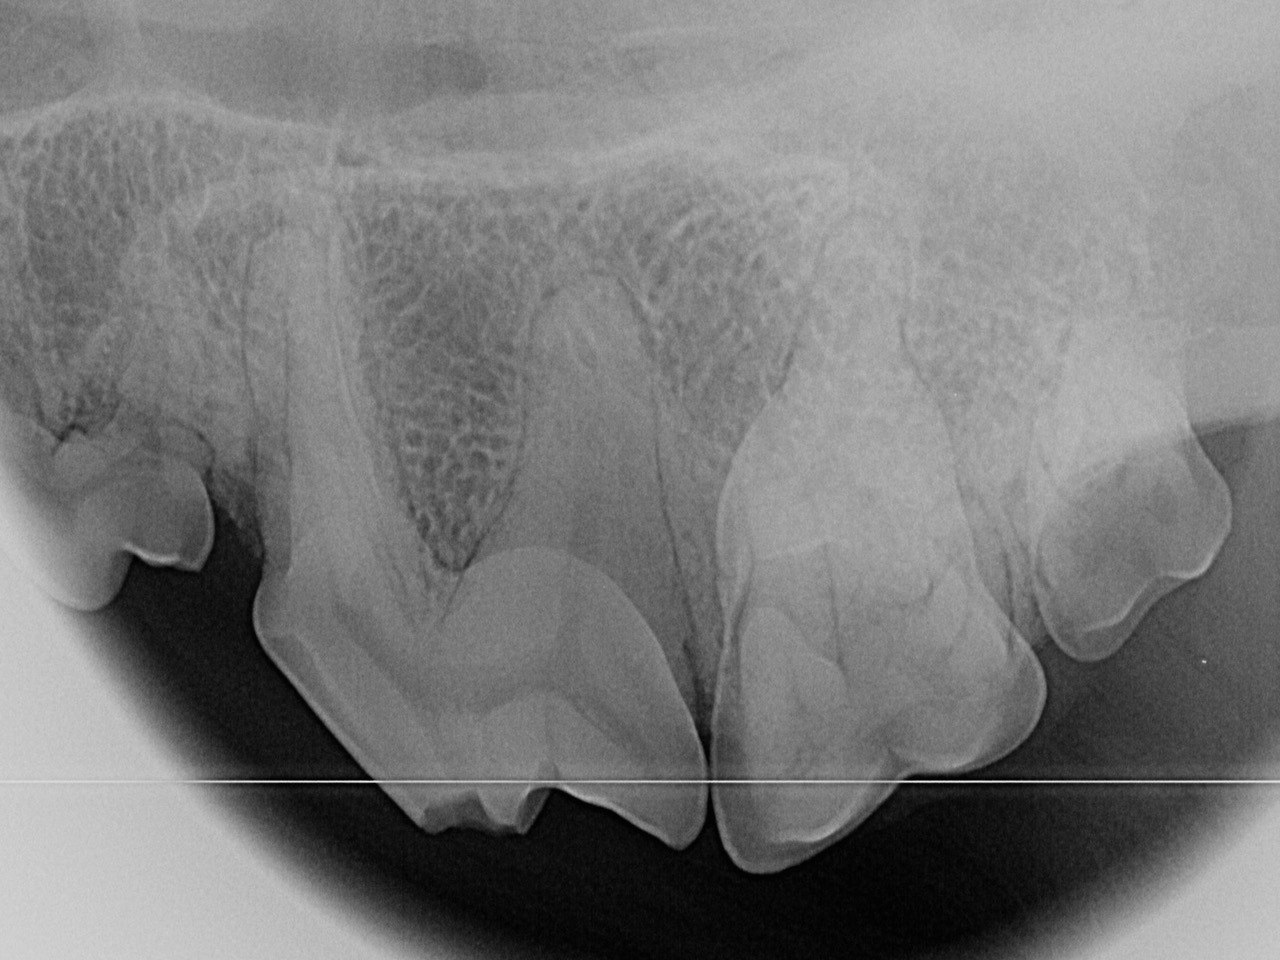

Zwei Wochen später ist es soweit: Mia wird zur Zahnstatuserhebung und Versorgung der Zahnfraktur in der Tierklinik vorgestellt. Nachdem sie in Frauchens Armen friedlich einschläft geht es in den Zahn-OP. Zuerst werden die Zähne mittels Ultraschall von Zahnstein und Plaque befreit. Im Anschluss werden - wie auch bei uns beim Zahnarzt - alle Zähne sondiert und geröntgt. Fast 30% aller klinisch wichtigen Befunde sind bei Hunden nur auf Dentalröntgen zu erkennen; bei der Katze sind es sogar noch mehr. Nur so kann der Tierarzt die Narkose ausreichend nutzen um alle für das Tier schmerzhaften Probleme zu behandeln.

Bei Mia gibt es außer der bekannten Zahnfraktur des linken Oberkieferreißzahns (Prämolarer 4) keine Auffälligkeiten. Bei der Sondierung und Betrachtung der Bruchkante mit der Lupenbrille zeigt sich, dass noch eine ganz feine Schicht Zahnsubstanz (Dentin) Mias Wurzelkanal bedeckt. Das Dentin bietet zwar noch einen gewissen Schutz, im Gegensatz zum Zahnschmelz (der beim gesunden Zahn die äußerste Schicht der Zahnkrone bildet) hat es jedoch feine Kanälchen durch die Bakterien eindringen könnten. Im Röntgenbild zeigt sich bisher kein Hinweis für eine bestehende Infektion, und zusammen mit der Besitzerin wird entschieden, dass Mia den Zahn erstmal behalten darf, aber in sechs Monaten erneut zur Zahnröntgenkontrolle kommen muss. Da die feine Dentinschicht über dem Wurzelkanal weder vor Infektionen noch vor Umwelteinflüssen schützt, wird die Bruchkante mit dem Bohrer geglättet und der Zahn mit Kunststoff versiegelt.